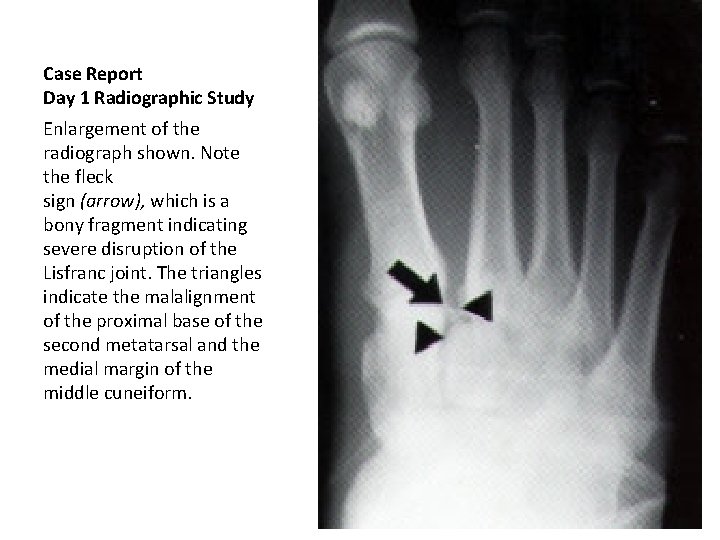

Case Report Day 1 Radiographic Study Anteroposterior weightbearing radiograph of the left foot of the patient in the illustrative case. The medial margin of the second metatarsal base and the medial edge of the middle (second) cuneiform, malaligned(triangles). A fleck sign (arrow) is also present.

Case Report Day 1 Radiographic Study Enlargement of the radiograph shown. Note the fleck sign (arrow), which is a bony fragment indicating severe disruption of the Lisfranc joint. The triangles indicate the malalignment of the proximal base of the second metatarsal and the medial margin of the middle cuneiform.